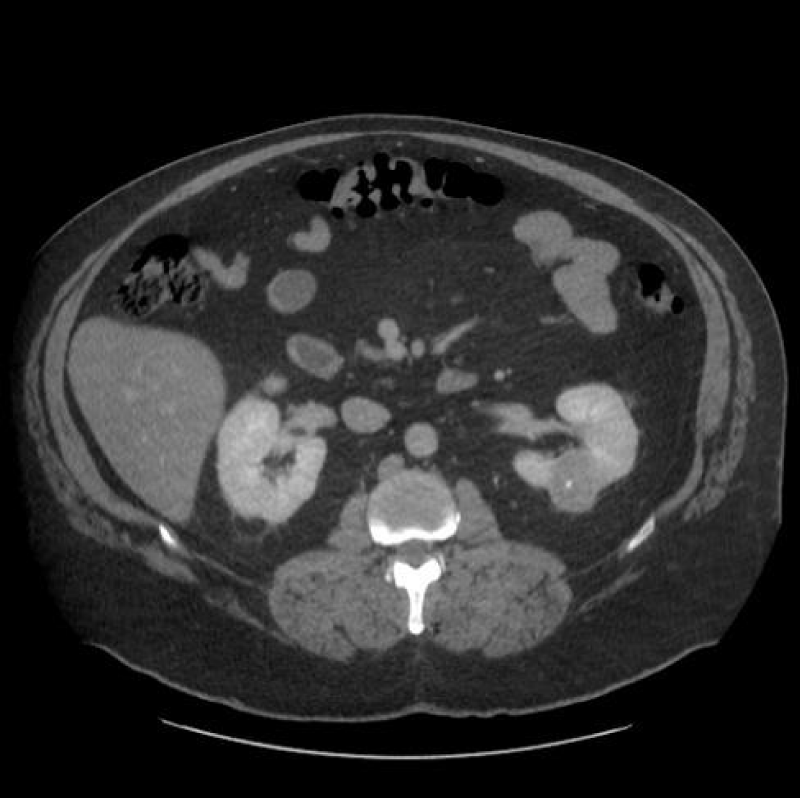

Renal cell carcinoma (RCC) is the ninth and fourteenth most common carcinoma in men and women respectively, alongside being the most lethal urological malignancy. RCC accounts for up to 90% of all kidney cancers, and up to 80% of all SRM. RCC constitutes Clear Cell (Figures 4-6), 75%, Papillary, around 15% to 20%, Chromophobe (Figures 7-9), 5% and other rarer subtypes. Clear Cell is the most common variant with the worst prognosis as it commonly presents at an advanced stage. Papillary type is more frequent in smaller lesion sizes [1,2,3,9-15].

Download Image

Figure 4: Clear Cell RCC of the upper pole of the right kidney.

Figure 5: Left renal Clear Cell RCC.

Figure 6: Right renal Clear Cell RCC.